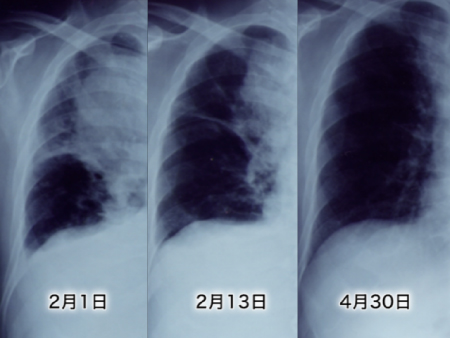

約10センチの右肺のがんは、見る見る小さくなった。

はじめに診断されて、3カ月後には、右肺上葉の原発巣はほとんど見えなくなった。